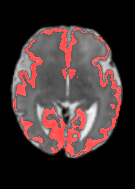

Fetal cortical plate segmentation is essential in quantitative analysis of fetal brain maturation and cortical folding. Manual segmentation of the cortical plate, or manual refinement of automatic segmentations is tedious and time-consuming. Automatic segmentation of the cortical plate, on the other hand, is challenged by the relatively low resolution of the reconstructed fetal brain MRI scans compared to the thin structure of the cortical plate, partial voluming, and the wide range of variations in the morphology of the cortical plate as the brain matures during gestation. To reduce the burden of manual refinement of segmentations, we have developed a new and powerful deep learning segmentation method. Our method exploits new deep attentive modules with mixed kernel convolutions within a fully convolutional neural network architecture that utilizes deep supervision and residual connections. We evaluated our method quantitatively based on several performance measures and expert evaluations. Results show that our method outperforms several state-of-the-art deep models for segmentation, as well as a state-of-the-art multi-atlas segmentation technique. We achieved average Dice similarity coefficient of 0.87, average Hausdorff distance of 0.96 mm, and average symmetric surface difference of 0.28 mm on reconstructed fetal brain MRI scans of fetuses scanned in the gestational age range of 16 to 39 weeks. With a computation time of less than 1 minute per fetal brain, our method can facilitate and accelerate large-scale studies on normal and altered fetal brain cortical maturation and folding.